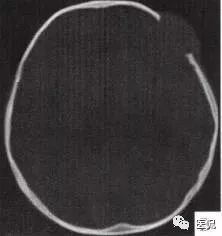

颅脑CT示:图A〜D,CT平扫示左侧额骨、蝶骨见溶骨性骨质缺损,边界清晰,周围无硬化边,伴有软组织肿块向脑外生长,边缘光滑,脑内无明显侵犯;

图H,为颅骨容积重建,提示类圆形骨质缺损,边缘光滑、整齐。